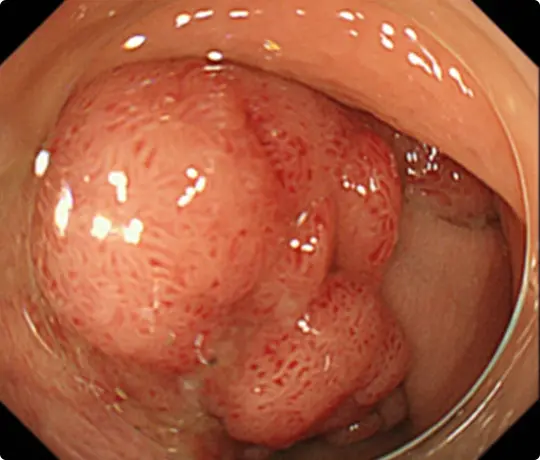

約3cmの大きな大腸ポリープです。

スネアでポリープの根元を縛り、電流を流して切除します(出血予防のためポリープの根元にクリップをうっています)。

切除した検体です。病理検査で早期大腸がんと診断されました。がんは完全に切除されており、治癒と判定されました。